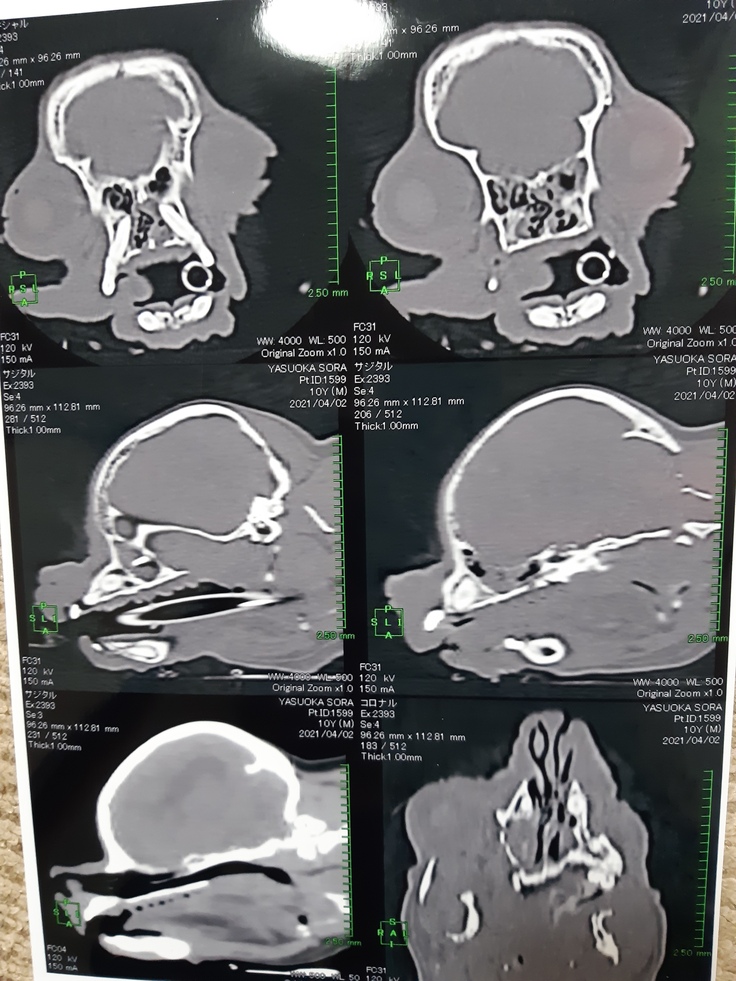

今日、空は鼻水の原因を見つけるためにCT検査をしました。

来週の心臓手術までに原因を見つけて治療をするためです。

結果ですが↓向かって右が空の画像で左は別の子の画像です。

赤丸で囲んでいるのが空の犬歯です、空の犬歯の生え方が鼻腔内に入るよに生えていて、歯からの炎症と言う結果となりました。

歯もこの先犬歯を抜いて治療をするようですが、まずは心臓の手術が優先なのでこのまま抗生剤と点鼻薬で手術まで様子を見ることになりました。

腫瘍などで無かったのは良い結果ですが、手術までに症状が落ち着いてくれて呼吸が安定することを願うばかりです。